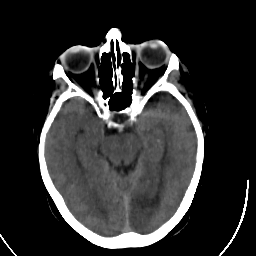

Stroke CT #3 -- Slice #9

[Home][Help][Clinical] Slice 9